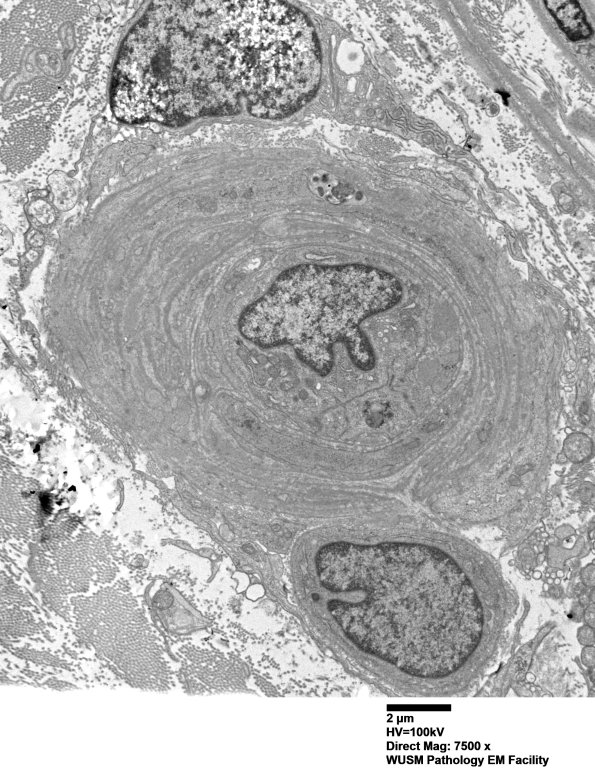

14B3A-C In this vessel the expansion of the vessel wall is largely composed of reduplicated intact and fragmented basal lamina. (electron micrographs)